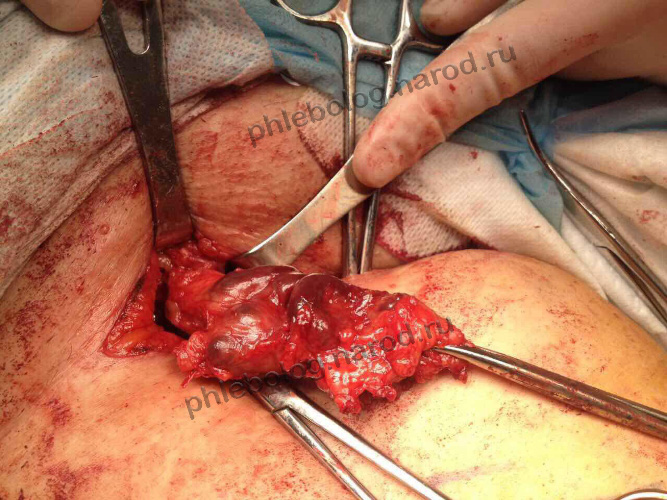

Оперировать рецидив варикоза

Так выглядит конгломерат варикозных вен в случае рецидива. Я проводил операцию после двух других докторов, боровшихся с варикозом до меня. Нелегкое это занятое - выдирать такие вены из рубцов. Да, потом был временный лимфостаз. Такое нужно оперировать сразу за один раз, чтобы потом уже не вмешиваться.